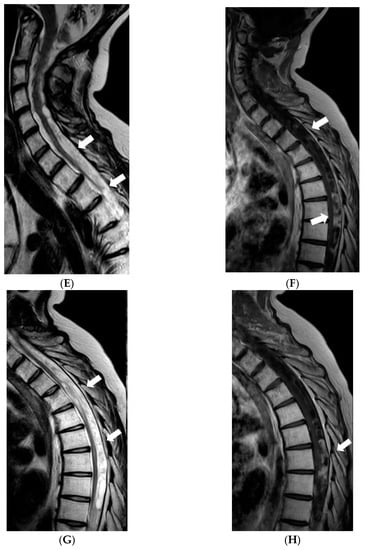

In 2017, follow-up brain MRI scans showed decreased leptomeningeal enhancement and slight decrease in size of cystic lesions in the brain; although, atrophy of the brainstem and cerebellum had progressed. However, spread of the tumour was found in the spinal canal through all its length manifested by diffuse meningeal enhancement and multiple cystic intra- and extradural lesions causing compression of the spinal cord. The girl received radiotherapy to the whole spinal cord; however, masses in the spinal canal progressed (Figure 5). In 2018, right-sided facial reconstructive surgery with medial cantopexy was performed.

Figure 5.

MRI of the spinal cord 6 years after the onset of symptoms: (A,D) Sagittal T2W, (B,E) T1W postcontrast images of the cervical and the upper thoracic spine, (C,F) postcontrast images of the middle/lower thoracic and the lumbar spine. In May 2017, (A–C) multiple confluent cystic extramedullary masses were found in the spinal canal through all its length, compressing the spinal cord at the level from C6 to T9 vertebrae. There was some nodular contrast-enhancement in the tumourous masses and diffuse meningeal enhancement. After radiotherapy in December 2017 follow-up MRI (D–F) demonstrated enlargement of the extramedullary masses in the lower cervical-upper thoracic spine with more vivid and diffuse enhancement, also, more vivid diffuse meningeal enhancement.